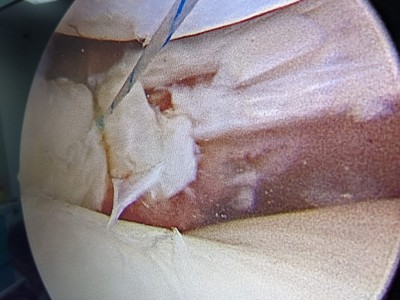

“Pacientul a suferit leziune gravă de menisc extern subluxantă, în langhetă, de corn posterior în totalitate și clivaj orizontal al părții medii meniscale externe. Am efectuat sutura de menisc extern, corn posterior, cu 2 ancore (prin tehnică în lasou) și partea medială, pentru ruptura veche în toartă de coș, ruptă după al doilea traumatism.

Procedura intervențională a fost minim-invazivă (laparoscopică), tehnica de sutură în lasou fiind ceea mai nouă și mai fiabilă (AOSS USA).

Așadar am ales tehnica chirurgicală de sutură a leziunilor complexe de menisc, pentru Theo Oprea, la care se adaugă protocolul francez de recuperare ameliorată, accelerată după chirurgia osteo-articulară, propus și practicat de mine în acest caz, după informarea consimțită a pacientului, despre beneficiile, riscurile și eventualele complicații ale acestui tip de intervenție chirurgicală, cu asumarea comună, pe baza unor scoruri de evaluare, pre și post-operatorie”.